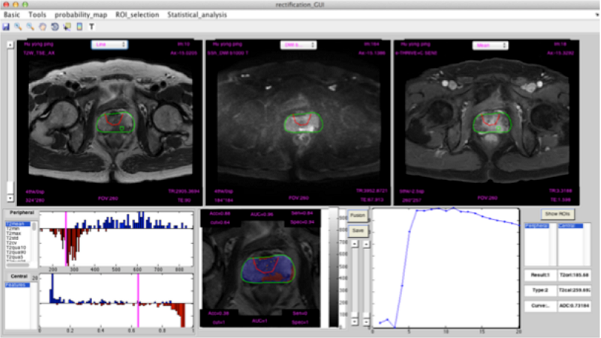

前列腺癌智能诊断平台软件界面

前列腺癌MR智能辅助诊断系统是一款智能学习和诊断的平台。该平台运用了人工神经网络的技术,从MR图像数据中挖掘出有用信息,让计算机可以从中“学到”肿瘤的影像表现。北京大学第一医院的影像专家对这套智能系统进行“训练”,通过图例和诊断结果来培训计算机,经过这种训练后,计算机就可以半自动地阅读图像。

在多参数磁共振影像中,通过提取图像中有用特征,找到最有可能是肿瘤的区域,做出肿瘤的风险预测。预测结果以概率地图的方式呈现,可以直观地帮助医生做出诊断。经过与病理结果的对照,证实了这种方法的准确性和有效性。